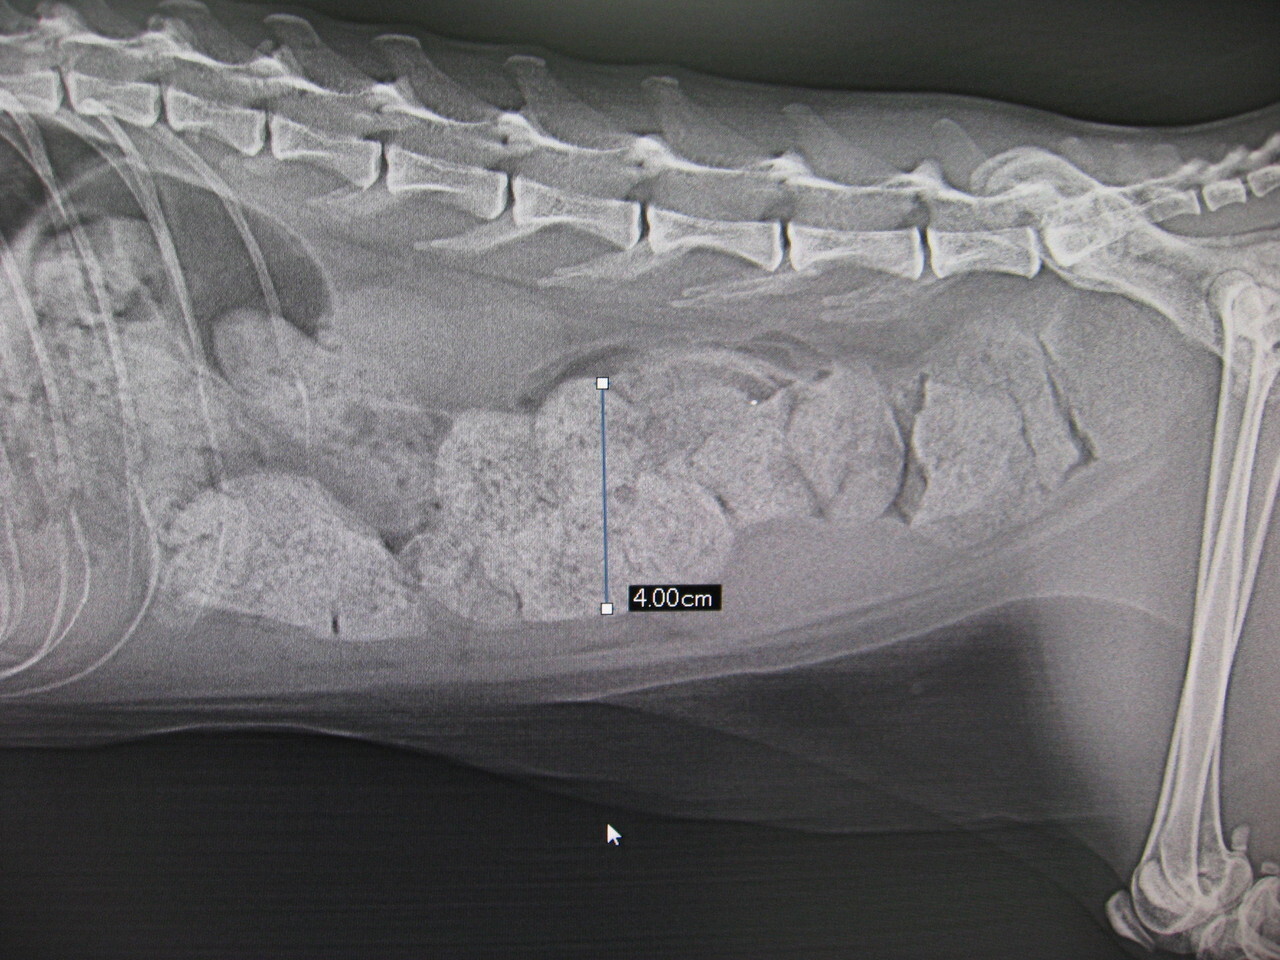

병원에서는 변비의 원인을 진단한 후 관장이나 완하제 투여 외에 항문에서 변을 나오게 하는 치료 등이 이루어집니다.

병원에 가지 않고 변비 고양이를 장기간 방치하고 있으면, 장내에 변이 자꾸 쌓여 버려, 대장의 일부인 결장이 거대화 하는 「거대 결장증」이 될 우려가 있습니다.

결장 내에 쌓인 변은 딱딱해져서 돌처럼 될 수 있는데, 이 경우 장을 절제하는 외과 수술을 할 수도 있습니다.